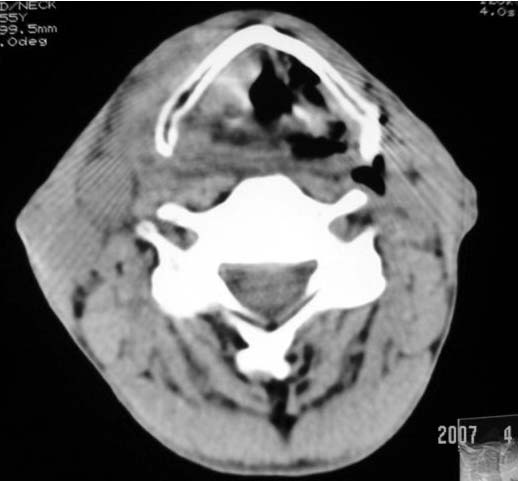

以下是引用dyqct在2007-4-20 16:19:00的发言:[br]考虑:1、左侧梨状窝区破裂伴左颈深、浅部气肿。[br] 2、右侧甲状腺区血肿(请追问病史是否伤及右颈部)。[br] 3、建议病情稳定后增强扫描除外右侧甲状腺腺瘤。